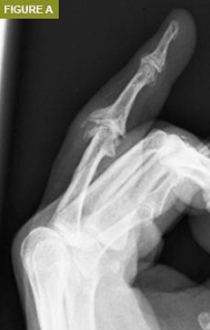

Daha önce de belirtildiği gibi, hasarlı veya tahrip olmuş eklemlerde eklem artroplastisi endikedir. Bu dejenerasyona bağlı olabileceği gibi daha önceki bir yaralanmanın sonucu da olabilir (Şekil A ve B). Romatoid artrit ve gut gibi inflamatuar artritlerin artan prevalansı ve birçok kişi tarafından benimsenen varlıklı yaşam tarzları ile eklem kıkırdağı dejenerasyonunun bir sonucu olarak ağrılı, şişmiş eklemler yaygın bir olaydır. Bu durumlarda eklem artroplastisi ağrıyı azalttığı ve hareket aralığını iyileştirdiği veya en azından koruduğu için faydalı olacaktır.